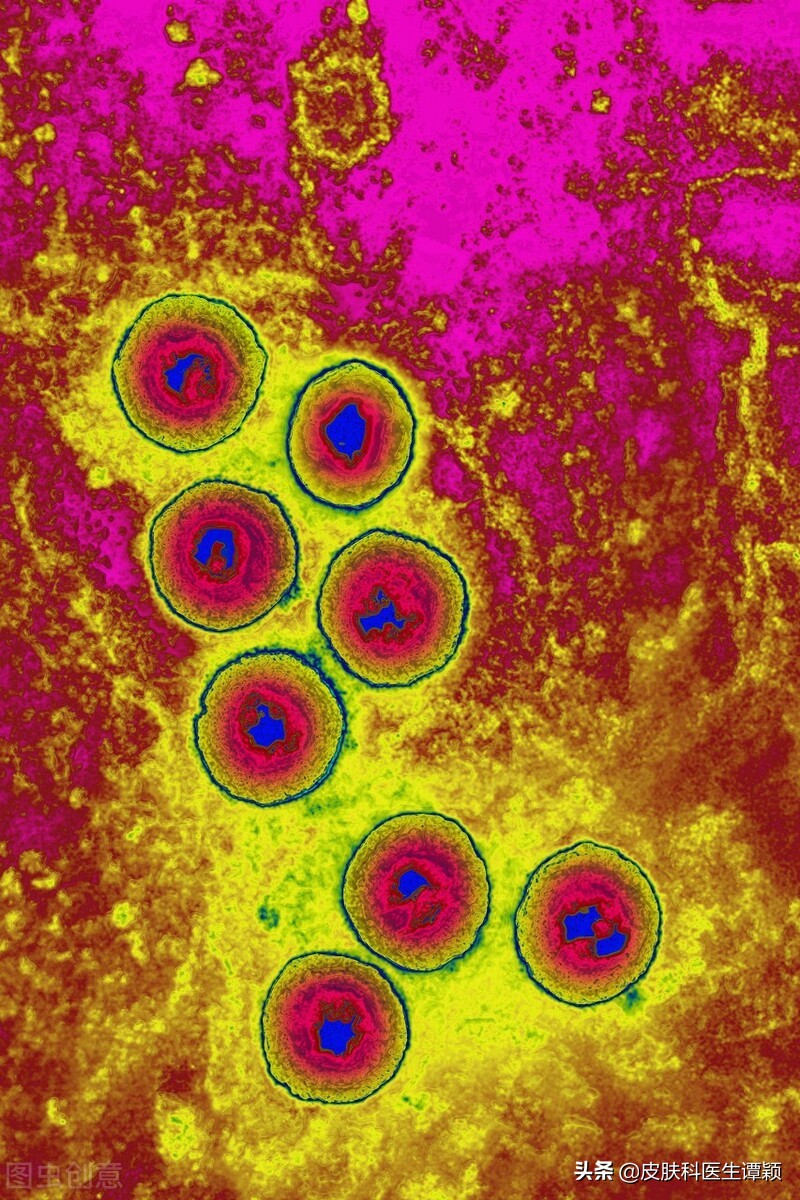

生殖器疱疹是一种较为常见的性传播疾病,是由单纯疱疹病毒(HSV)感染生殖器、肛周等部位皮肤黏膜所引起,其中II型单纯疱疹(HSV-II)是主要的感染亚型。

在近几十年以来,生殖器疱疹逐渐发展为目前“最常见”的一种性传播疾病,它能通过皮肤黏膜的直接接触而传染,患者和无症状病毒携带者是主要的传染源。